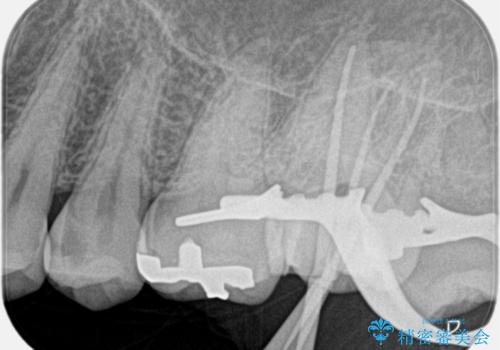

【精密根管治療】奥歯がズキズキ痛い。

- 奥歯がズキズキ痛いことを主訴に来院されました。

治療にて歯髄は保存できないと判断したため、根管治療を行いセラミッククラウンにて修復しております。

自発痛の既往がある場合は、抜髄の適応となることが多いです。